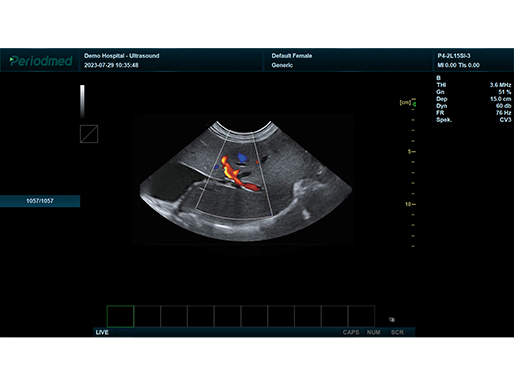

微凸探头-彩色多普勒模式-脾 狗

彩色多普勒模式 脾 狗